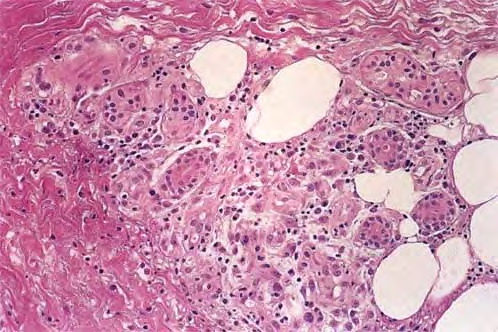

Neutrophilic eccrine hidradenitis = التهاب الغدد العرقية الناتحة بالمعتدلات

OLYMPUS DIGITAL CAMERA